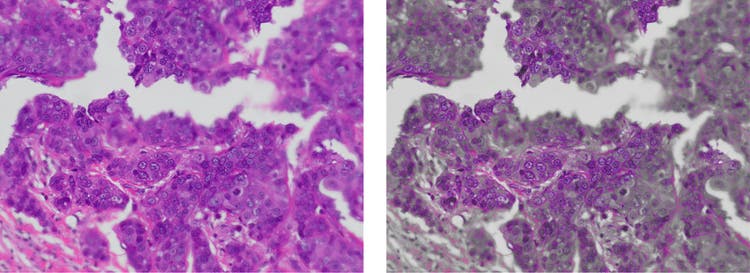

Alcance de enfoque (Focus peaking): permite identificar, a través de una ayuda de enfoque visual, la región de la muestra que está siendo enfocada. Las áreas enfocadas se mostrarán en color y las áreas desenfocadas proyectarán una superposición gris en una imagen en vivo. Esta característica es particularmente útil para observar muestras gruesas.

Alcance de enfoque en cámaras microscópicas

Sin alcance de enfoque (izquierda) versus con alcance de enfoque